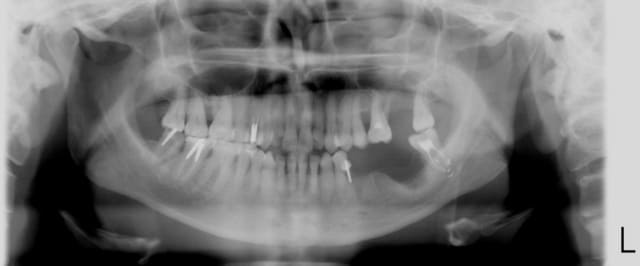

pour situer le danger:

j'ai posé un PX, donc pour os peu dense, en sous forant ++.

il est rentré comme de rien. Je retire le préhenseur d'implant, en maintenant le bord de l'implant avec mon decolleur (j'avais peur qu'il ressorte).

je décide alors de tester la stab primaire avec ma sonde paro, très doucement et...trop tard il a filé direct!

Ça faisait un moment que j'avais un excès de confiance, ça m'a bien remis les pieds sur terre!

Si effectivement ça peut vous servir, méfiez vous des zones sous sinusienne avec os peu dense et cortical du sinus peu visible: cf pano jointe.